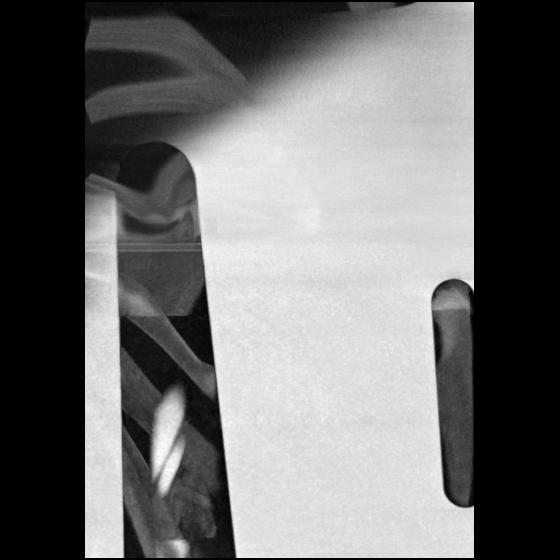

23 ANGIO,CE,Cor-MIP,5.000,ANGIO,Cor-MIP,